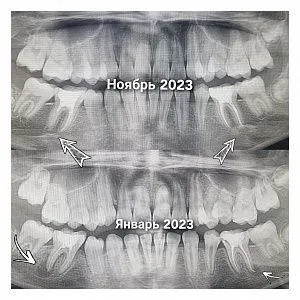

До и после

Работы специалиста